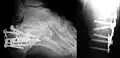

Le calcanéus peut subir des fractures.